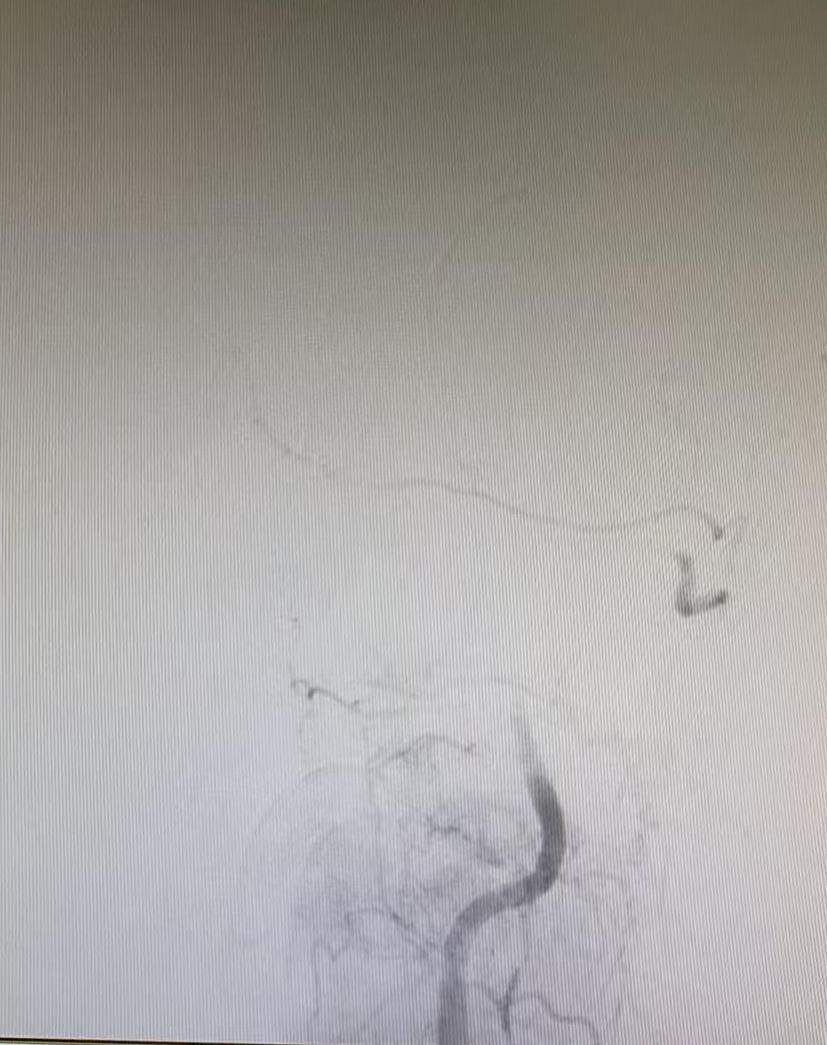

與家屬充分溝通并取得同意后,晚上7點(diǎn)42分,患者被推入介入手術(shù)室。手術(shù)團(tuán)隊(duì)經(jīng)驗(yàn)豐富,操作精準(zhǔn),晚上7點(diǎn)50分成功建立手術(shù)通路,在DSA影像引導(dǎo)下,微導(dǎo)絲與微導(dǎo)管精準(zhǔn)穿越閉塞血管段。晚上8點(diǎn)07分,堵塞的椎基底動(dòng)脈被成功開(kāi)通,從進(jìn)入介入室到血管再通,僅用時(shí)25分鐘。

但挑戰(zhàn)還在繼續(xù),血管開(kāi)通后發(fā)現(xiàn)內(nèi)部存在嚴(yán)重狹窄,遠(yuǎn)端血流灌注不足,團(tuán)隊(duì)隨即進(jìn)行球囊擴(kuò)張改善血流,但血管回縮明顯。為確保持久通暢,團(tuán)隊(duì)果斷植入一枚支架。最終,血管形態(tài)恢復(fù)良好,血流達(dá)到最佳標(biāo)準(zhǔn),缺血的大腦獲得了充足的血液供應(yīng)。

術(shù)前血管閉塞

球囊擴(kuò)張術(shù)后

支架置入后

一場(chǎng)集腦動(dòng)脈造影、顱內(nèi)動(dòng)脈取栓、球囊擴(kuò)張與支架置入于一體的多模態(tài)手術(shù)順利完成。